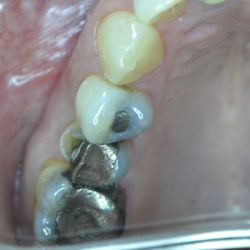

Ο προγόμφιος της φωτογραφίας υπέστη κάταγμα του παρειακού φύματος λόγω εκτεταμένης παλιάς έμφραξης αμαλγάματος.

Προκειμένου να αποφευχθεί ο τροχισμός του δοντιού για τοποθέτηση στεφάνης, διαδικασία που μπορεί να οδηγούσε σε νέκρωση του δοντιού, αποφασίστηκε η αφαίρεση της παλιάς έμφραξης αμαλγάματος και η αποκατάσταση του δοντιού με ένα επένθετο εργαστηριακής σύνθετης ρητίνης.

Ο εκτροχισμός που απαιτήθηκε για αυτή την διαδικασία ήταν ελάχιστος, έτσι το δόντι διατηρήθηκε ζωντανό χωρίς προβλήματα.